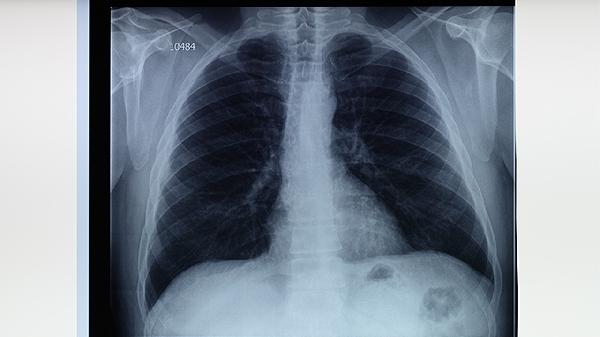

肺結核患者出現(xiàn)大咯血、厚壁空洞、結核性膿胸或藥物治療無效等情況時,通常建議手術治療。肺結核手術治療的適應癥主要有大咯血、厚壁空洞、結核性膿胸、支氣管胸膜瘺、藥物治療無效的局限性病灶等。

厚壁空洞指空洞壁厚度超過3毫米且經(jīng)6個月規(guī)范抗結核治療未閉合的病灶。這類空洞易成為持續(xù)排菌源,可能引發(fā)咯血或繼發(fā)感染。手術方式多選擇肺段切除術,術前需通過痰涂片確認排菌狀態(tài)。術后仍需完成抗結核療程,常用藥物包括異煙肼片、利福平膠囊等。

結核性膿胸患者出現(xiàn)胸膜增厚、肺不張或混合感染時需手術治療。慢性膿胸可能導致胸廓塌陷和呼吸功能障礙,表現(xiàn)為持續(xù)性胸痛、低熱等癥狀。手術方式包括胸膜纖維板剝脫術或胸廓成形術,術中需清除壞死組織。術后需繼續(xù)使用吡嗪酰胺片等抗結核藥物,并配合胸腔引流。